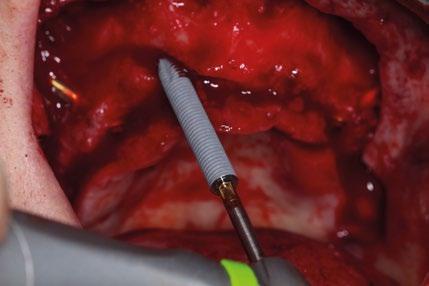

8.- Realizamos osteotomía mediante férula quirúrgica utilizando fresa piloto. (Figuras 22 a 24)

9.- Seguimos preparando el lecho utilizando fresado biológico con la OsseoShaperTM. (Figura 25)

10.- Colocamos implante Nobel Biocare N1TM TiUltra de 3,5x13. (Figura 26)